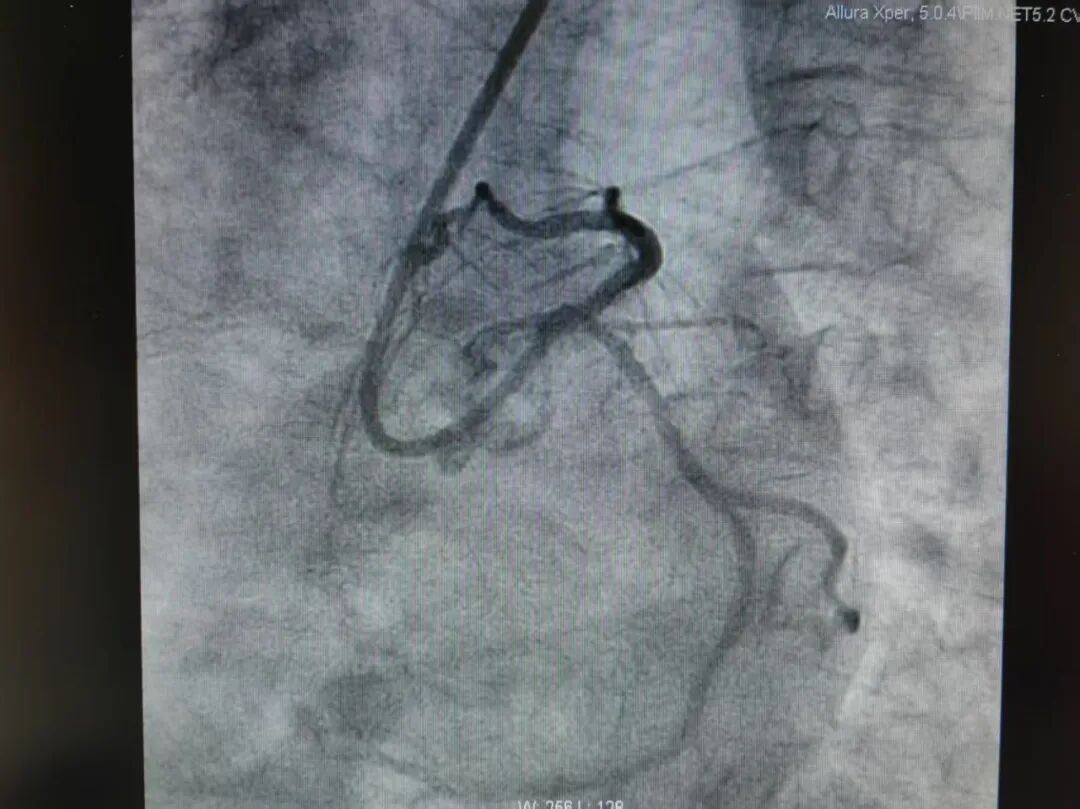

据悉,患者为老年女性,间断性胸痛症状已持续10年有余,近1周来病情加重,胸痛发作愈发频繁,活动耐力明显下降,严重影响日常生活。该患者有10年高血压病史,2022年曾因胸痛在外院接受冠脉造影检查,提示冠脉三支病变,当时医生为其回旋支及右冠状动脉植入支架以缓解病情,但前降支存在弥漫钙化伴不规则狭窄病变,狭窄程度最重达80%,因病变复杂暂未进一步处理。此次入院后,冠脉 CTA 检查提示前降支重度狭窄,进一步冠脉造影确诊该血管弥漫钙化伴狭窄,狭窄程度已进展至95%,属于高危复杂病变。

在介入治疗过程中,团队遇到了棘手难题:由于前降支钙化严重、血管管腔极度狭窄,最小型号的扩张球囊也无法顺利通过病变部位,常规支架植入手术难以实施。面对这一困境,冯源海主任团队与葛海龙教授紧急讨论,结合患者病情特点,最终确定采用冠脉旋磨术这一先进技术方案。

手术中,葛海龙教授全程指导,冯源海主任团队精准操作,经过精准旋磨后,前降支管腔狭窄程度得到显著改善,血流通畅性恢复,随后团队顺利完成球囊扩张及支架植入术。整个手术过程顺利,患者生命体征平稳,术后恢复良好,胸痛症状已明显缓解。